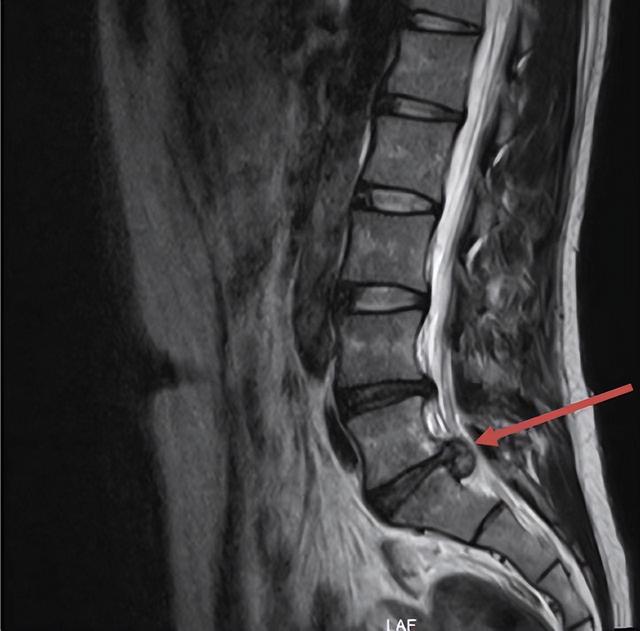

打篮球、游泳、跑步等 , 他统统安排上 。 近2个月下来 , 小金体重减轻、身体也结实了 , 但离“脱衣显(肌)肉”仍遥遥无期 , 于是他发狠 , 一头扎进健身房“加餐” 。 发病前5天 , 他正在负重深蹲(杠铃)后 , 突然出现左侧臀部疼痛 , 左下肢无力 , 麻木为膝关节以下麻木 , 小金当即去了附近医院 。 医生予以激素抗炎、甘露醇脱水等治疗 , 症状稍缓解 。 为求进一步治疗 , 小金来到浙江省人民医院神经外科就诊 。 结果腰椎核磁共振检查提示:腰4/5椎间盘突出 , 腰5/骶1椎间盘脱出 , 椎管狭窄 , 与不当运动有关 。小金得知病因 , 很是懊悔 。

小金被诊断为负重弯腰后出现的急性腰椎间盘脱出 。 经过充分准备后 , 雷兵主任、主任医师麻育源、副主任医师杨开创等 , 给小金做了手术 , 术后疼痛症状立即消失 , 第二天即可下床 , 5天便出院 。

雷兵主任介绍:腰椎间盘突出症是因腰椎间盘的退变 , 同时纤维环部分或全部破裂 , 髓核突出压迫或刺激神经根及马尾神经所引起的一种综合征 , 是引起下腰痛和腰腿痛的最常见原因 , 严重的甚至会出现跛行、大小便功能障碍等 。